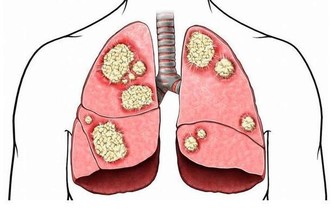

肺癌是中國發病率最高的癌症,也是死亡率最高的癌症。不管是何種癌症,我們都知道,一般發現時都是晚期,很難治愈。如果癌症早期能夠及時發現,經過治療後的五年生存率會大大提升。對於患者來說疾病的早發現要比“靈丹妙藥”見效好!

69歲的Bill Mcwhite,去年夏天到德克薩斯州莫斯科灣沿岸度假,本想著藉此機會好好放鬆一下自己,但整個旅程都被慢性阻塞性肺疾病(也稱為COPD)“破壞”!胸部出現阻塞症狀並伴隨著呼吸困難,這讓Bill不得不住進了醫院。

在德克薩斯州旅行結束後,Bill決定要仔細檢查一下自己的肺,畢竟他是一位有著55年菸齡的老煙民。在找到梅奧診所健康系統肺科的Adel Zurob醫生,醫生了解情況後建議Bill做一項肺癌篩查(低劑量CT)。檢查結果顯示:右肺有一個小的癌變結節。通過進一步的正電子發射斷層掃描(PEC-CT),顯示肺部以外沒有擴散或轉移的徵象。醫生建議,立即進行手術治療。